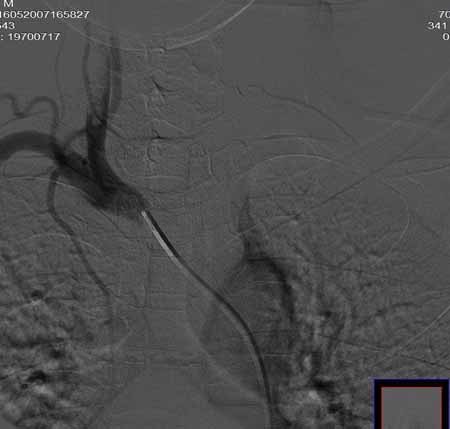

右侧颈总动脉闭塞(血栓形成),左侧大脑前动脉侧支、前交通动脉供应右侧大脑半球

右侧颈总动脉闭塞

右侧颈总动脉闭塞 ,左侧大脑前动脉侧支、前交通动脉供应右侧大脑半球,后交通部分开放 。缓慢代偿血流,分级3

右侧颈总动脉内见充盈缺损,提示血栓/栓子,原因:

1注意有无心房粘液瘤/血栓

2大动脉炎

抗凝治疗

右侧颈总a闭塞,右颈内颈外未显影,左侧未见异常,并通过wills环代偿右侧大脑半球血供